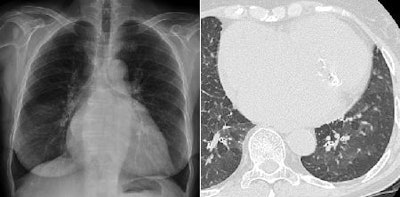

| Chest digital tomosynthesis detected lung calcifications (left) as verified by CT (right). Images courtesy of Dr. Emilio Quaia. |